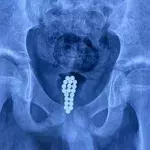

On returning home she noticed an abnormal pattern emerging in her skin that led her to question if it could be more than just a rash. She immediately made an appointment at the hospital and what they found was nothing less than shocking.

After checking over the strange marks on her thigh, the doctors made a horrifying discovery. Something was trying to eat its way through her flesh! Thankfully, medical intervention prevented the situation from getting out of hand... We bet she’s had enough of holidays after this one.